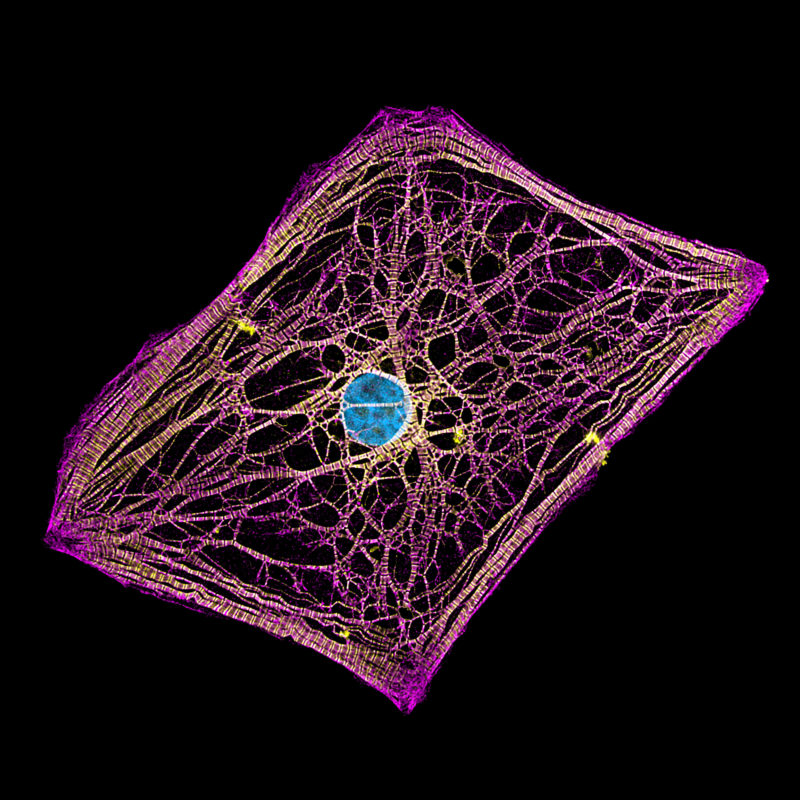

Image Analysis Technique Provides Better Understanding Of Heart Cell

Plant Cell Diagram Understanding The Intricacies Of Plant Cells De